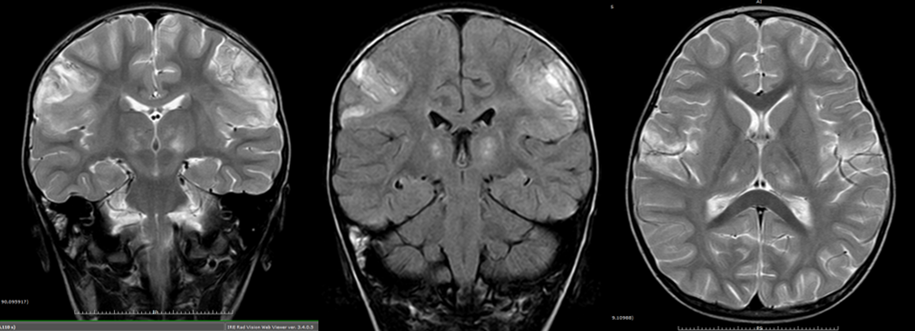

• 26/06: se realiza resonancia magnética (RM).

RM del 26/06. Alteración de la señal (hiposeñal en IPTI e hiperseñal en ponderaciones de TR largo bilateral cortical de lóbulos parietales (precentrales) y de ganglios de la base (tálamo/pulvinar) en relación con edema/exudado inflamatorio). En las secuencias ponderadas en TI se observa un aumento de la señal, añadidas a zonas de menor señal que, en la secuencia de T2, restringe la señal. Sugestivas de zonas de hemorragia liminar en relación con una probable necrosis cortical laminar bilateral. Estas zonas presentan un realce tras la administración de contraste (cortical y meníngeo), sugiriendo la persistencia de comportamiento inflamatorio-vasculítico necrotizante activo. No hay colecciones focales.